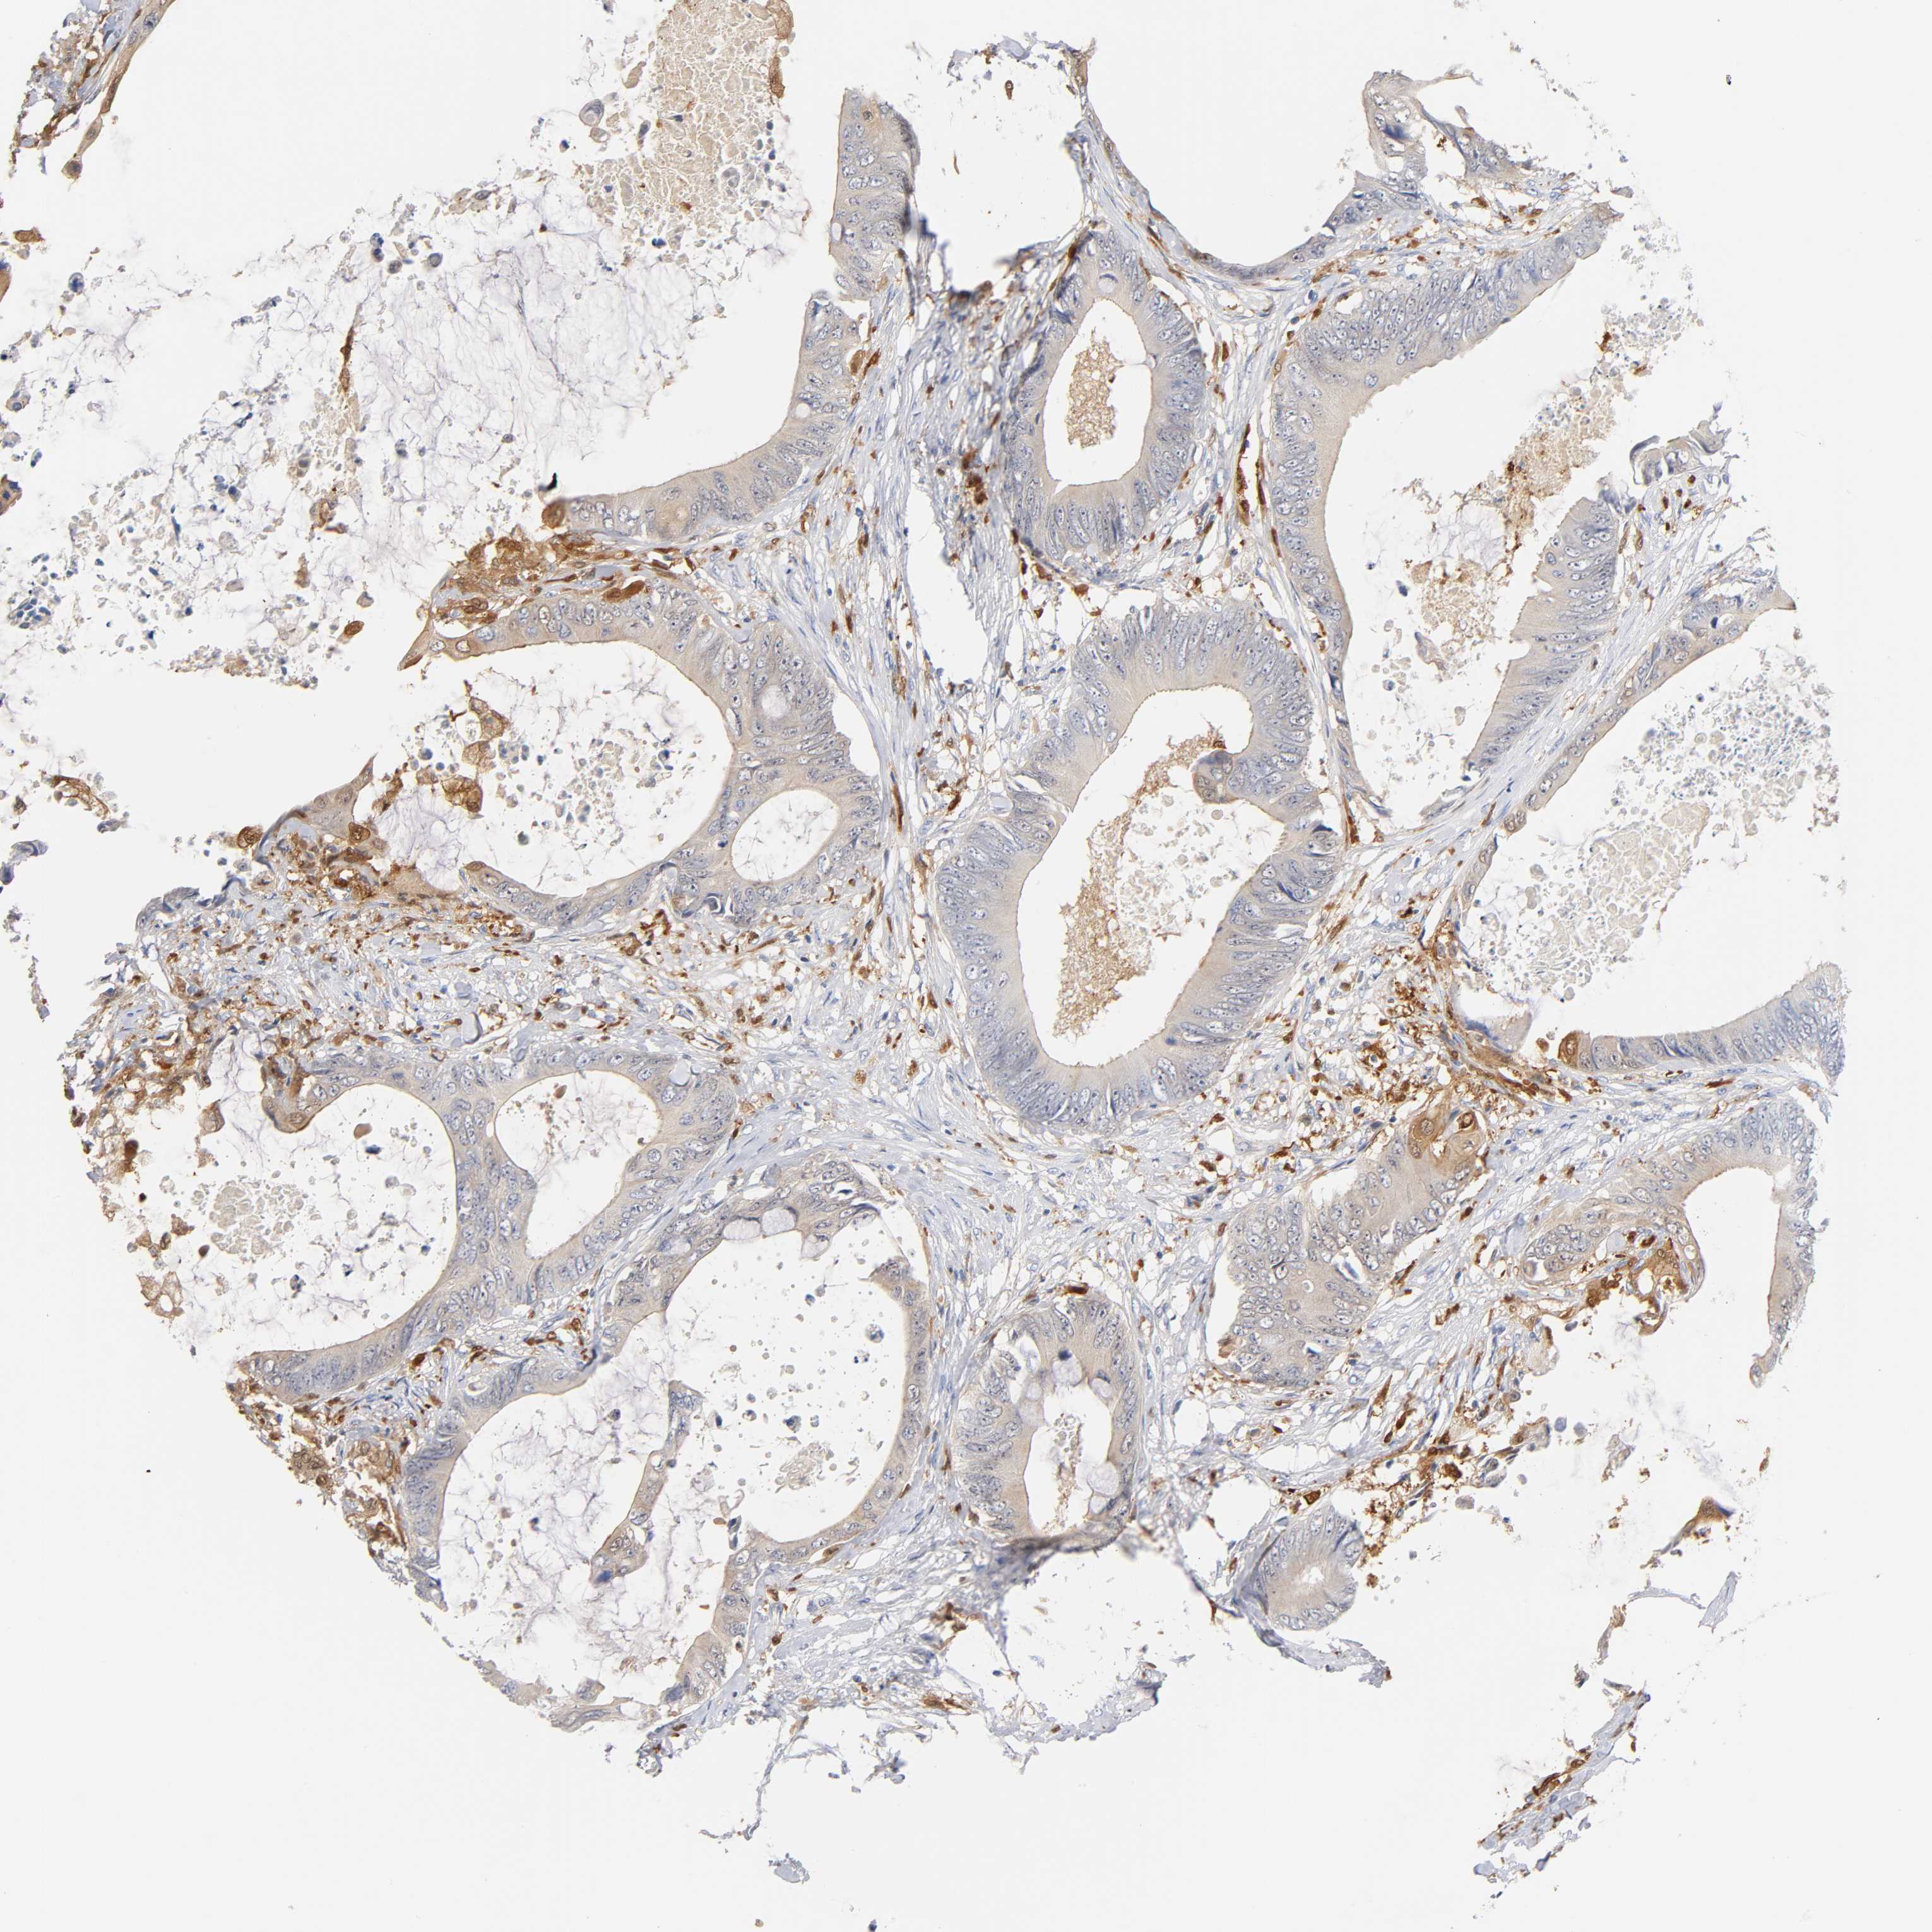

CANCER COLORECTAL CANCER Show tissue menu

Colorectal cancer

Human cancer

Colon adenocarcinoma

Rectum adenocarcinoma